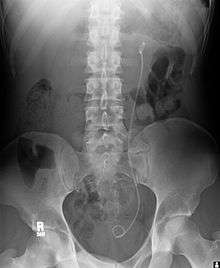

| Ureteral stents are used to ensure the patency of a ureter, which may be compromised, for example, by a kidney stone. This method is sometimes used as a temporary measure to prevent damage to a blocked kidney until a procedure to remove the stone can be performed. | ![]() Example of a uretal stent used to alleviate hydronephrosis of the kidney |